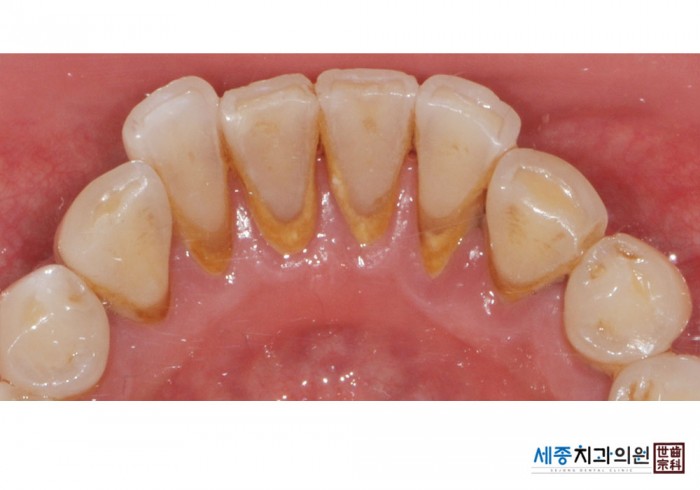

[스케일링] 치주질환 예방 스케일링

치료전 : 2015-08-05

가글마취&저주파 스켈러를 사용한 착색제거 스케일링